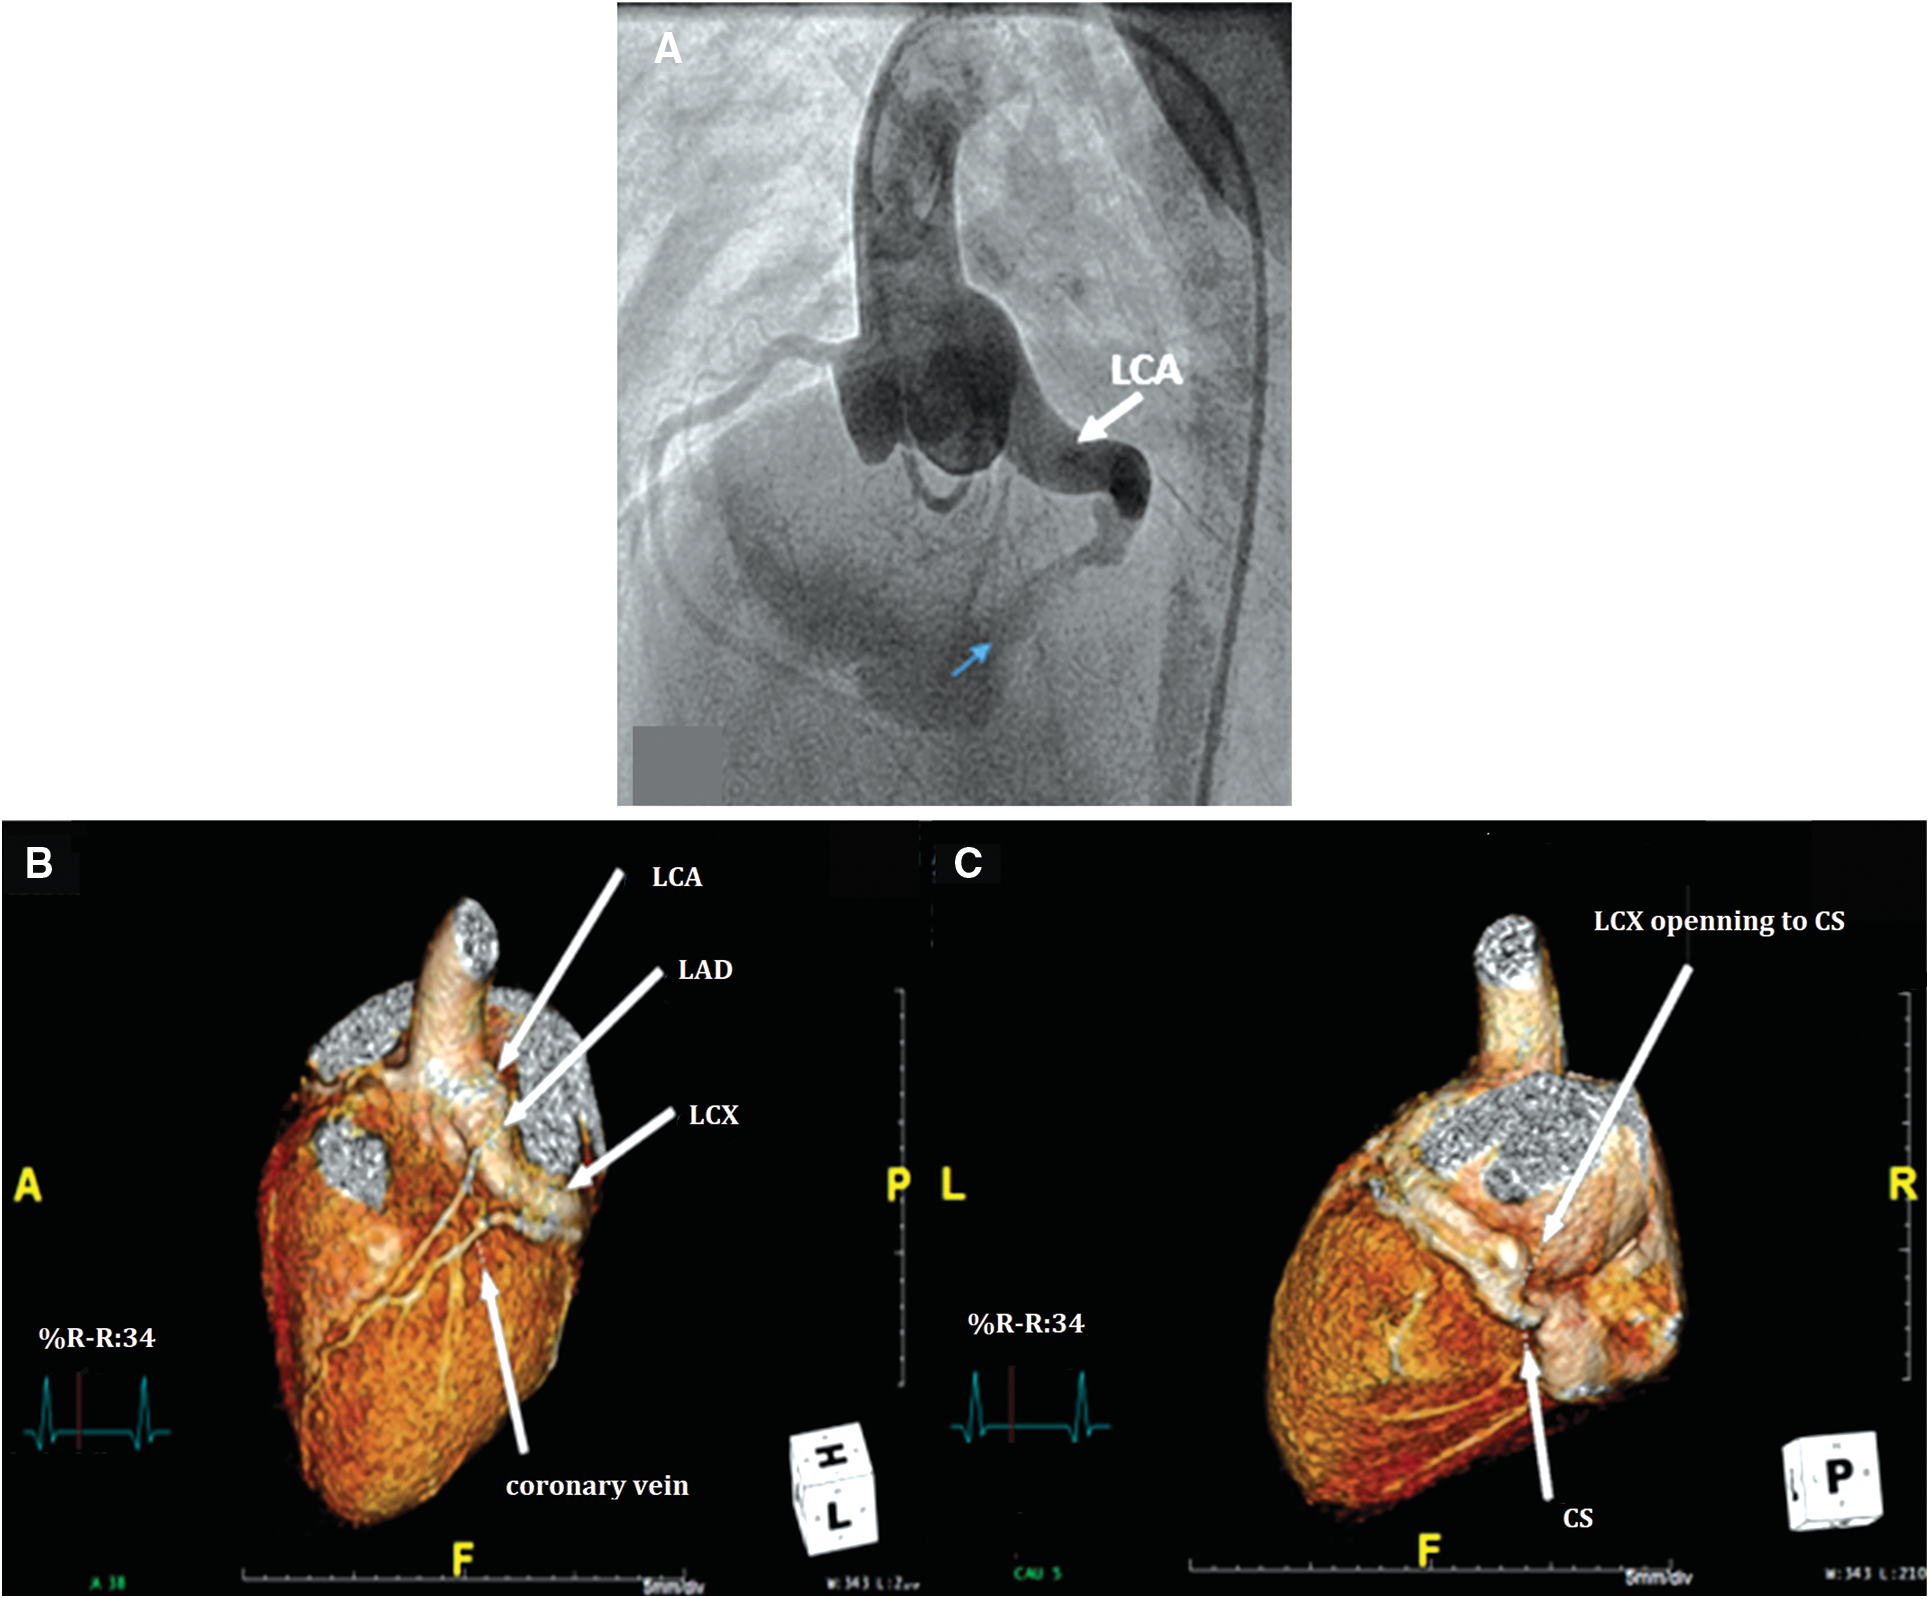

Primary treatment with SC was chosen for 7 patients [median age at diagnosis of 1 month (range 4 days–7 years)], all of whom had isolated CCAF with symptoms of heart failure. All of the preoperative TTEs showed good LV function. The median age at the time of the repair was 2 years (range 1 month–9 years). A complex fistula (i.e., 2 openings) was noted in one patient. All patients had dilated fistulous tracts and one had the drainage site to the coronary sinus (Fig. 2). The surgical procedures included surgical ligation/direct closure (n = 5), pericardial patch closure (n = 1), and fistulous ligation with aneurysmorraphy (n = 1). In addition, three patients underwent surgical ligation subsequent to the attempted PC, as previously described. Ten patients who underwent SC had no operative mortality. The median cardiopulmonary bypass and cross clamp time was 34 min (range 15–86 min) and 15 min (range 10–54 min), respectively. Postpericardiotomy syndrome and transient asymptomatic ST depression was noted in one patient. Average hospital length of stay was eight days (including a pre-operative day). At the median time of follow-up [3.3 years (range 0.1–8 years)], the ten patients survived without ischemic heart or heart failure symptoms. Four patients had postoperative CCT and CMR surveillance. Two patients with post-operative thrombus formation in the dilated fistulous tract had a stenosis of the distal coronary artery without perfusion deficit and they had preserved LV function. Characteristics of the original CCAF were complex: 2 large openings in 1 patient and a large-diameter drainage site with a dilated distal coronary artery in one patient (Figs. 3 and 4) (Table S1).

Figure 2: Pre-operative images of congenital coronary artery fistula (CCAF) from left circumflex artery (LCx) to coronary sinus (CS) in a 6-year-old boy. A. Aortic root angiogram demonstrating the dilated left coronary artery (LCA) with tortuous CCAF to the CS opening (blue arrow); B, C. Reconstructed cardiovascular computerized tomography showing CCAF from LCx to CS with tubular ectasia of LCA (LAD, left anterior descending artery)